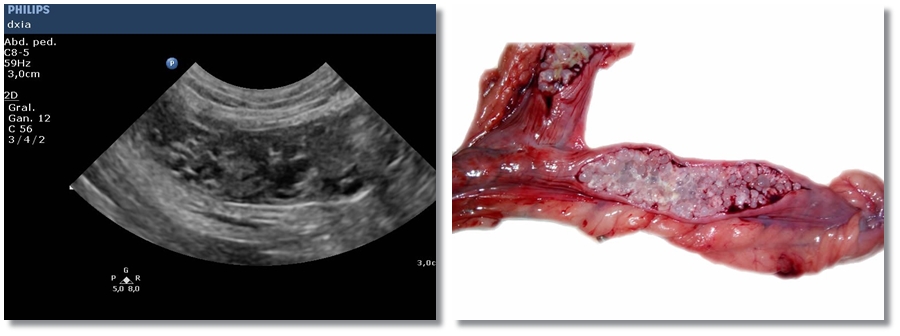

Tumor Explénico / Tumor de Bazo

Paciente con distensión abdominal junto con apatía que presenta ligera anemia en analítica. Se realiza…